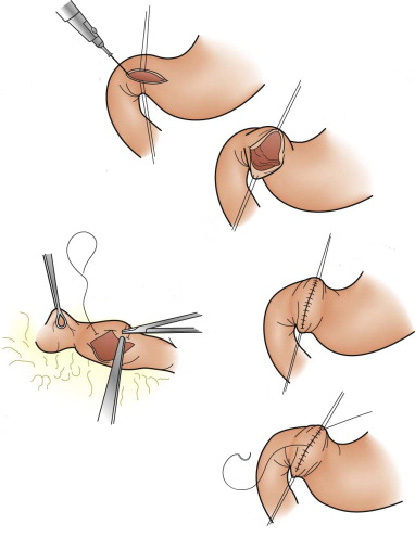

Mucosectomia é o procedimento realizado quando há necessidade de retirada de lesões maiores do trato gastrointestinal.

O exame de Mucosectomia é realizado através de injeção de liquido embaixo da lesão, através de uma agulha específica. Com isso a lesão se destaca das camadas mais profundas do intestino, diminuindo o risco de perfuração.

A retirada da lesão é feita com uma alça de polipectomia e o material é encaminhado para estudo anatomopatológico (no microscópio) da mesma forma que ocorre nas biópsias.

Polipectomia com pinça

Pequenos pólipos podem ser removidos com segurança usando-se apenas uma pinça.

Polipectomia com alça diatérmica

Pólipos maiores necessitam ser removidos com alça e corrente de cauterização. Este procedimento permite cortar a base do pólipo e ao mesmo tempo coagular o local para evitar sangramentos.

Porém alguns pólipos possuem a base (pedículo) largo onde passam vasos calibrosos e por isto tem risco aumentado de sangramento na retirada mesmo usando a corrente de coagulação.

Nestes casos algumas medidas podem ser realizadas para diminuir o risco de sangramento:

Injeção de adrenalina na base do pólipo

Colocação de um laço na base do pólipo para estrangular o pedículo

Alguns pólipos são tão grandes que não podem ser removidos inteiros. Nestes casos o pólipo é retirado em pedaços para poder garantir a sua remoção completa.

Alguns pólipos não possuem a base alongada (pedículo), estes são chamados de pólipos sésseis. A remoção destes pólipos possui risco maior de perfuração do órgão pois como são planos ficam muito próximos da parede externa do órgão.

Mucosectomia

Para diminuir este risco, injeta-se com um uma agulha uma solução abaixo do pólipo para que ele levante e fique mais longe da parede do órgão. Após isto passa-se a alça diatérmica e realiza-se o

procedimento de polipectomia.